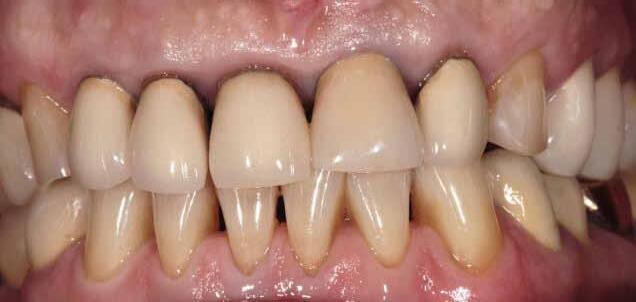

A significant number of people are unhappy with their smile, which has a considerable psychosocial impact. Although many seek cosmetic dental treatment, costs, fear and duration of total treatment are often barriers to the patients. Nevertheless, many could benefit from small and subtle changes to their teeth. With simple direct and freehand techniques, quick but significant results can be obtained that ultimately greatly improve the overall smile aesthetics.

The restoration of abfractions in the anterior area is important for aesthetic appearance especially in patients with high smile lines. Moreover, restoring abfractions strengthens the cervical area of the tooth, prevents further loss of enamel and ameliorates unpleasant sensitivity.

Black triangles and diastemas can cause entrapment of the food and accumulation of bacteria, which leads to gingivitis and ultimately periodontitis. By eliminating the black triangles and diastemas with composite bonding, the dentist not only improves the aesthetics, but also protects the long-term health of the periodontal tissues.

Worn canine cusp restoration is of special functional importance. Creating functional canine guidance with a minimally invasive composite addition to the canine cusp will protect the posterior teeth during lateral movements of the jaw. Incisal wear restorations return the youthful appearance to the smile and prevent further loss of enamel and exposure of the dentinee.

Restoring incisal wear and closing diastema with G-aenial A’CHORD. Courtesy of: Dr Aleksandra Slacan, Poland

Reshaping of teeth and diastema closure with G-aenial A’CHORD. Courtesy of: Dr Andres Silva, Spain